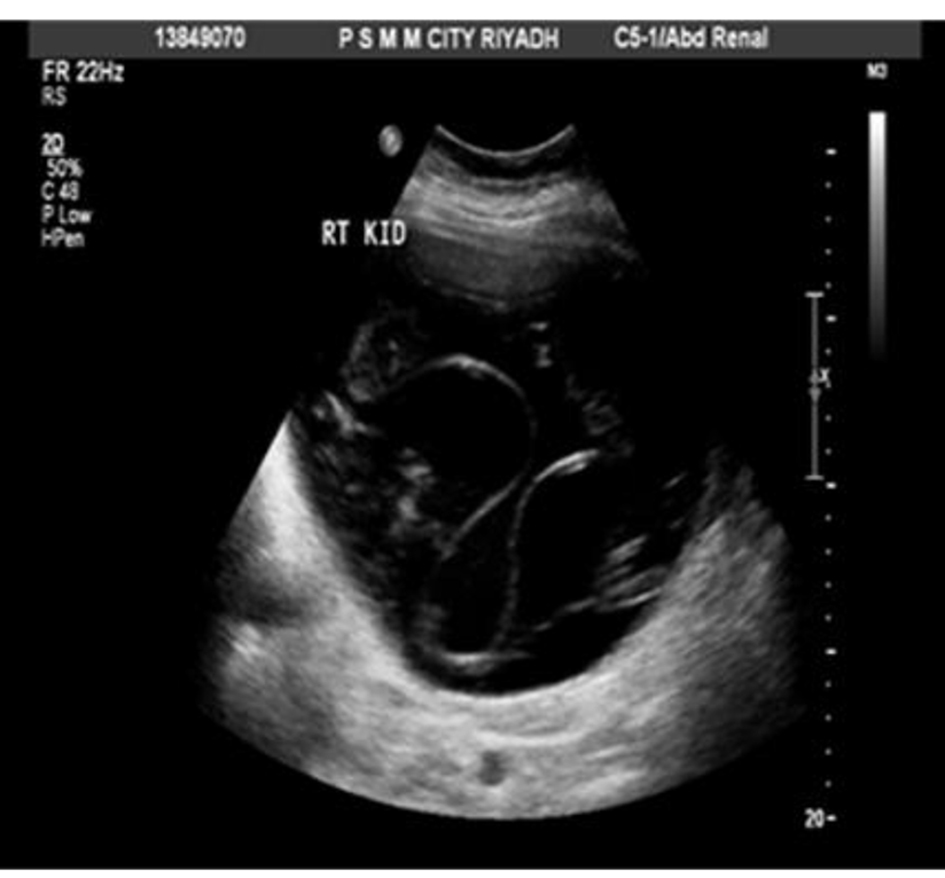

A 65-year-old woman with DM and hypertension was admitted to hospital with 8 years history of right lumbar pain. She used to live in the desert with strong history of contact with animals including dogs. She denied any urinary or other systemic symptoms. General examination was normal. Abdominal examination showed a 7 × 6 cm paraumbilical hernia. US abdomen showed a complex cystic structure measuring 20 × 9.4 cm occupying the right renal region that revealed multiple septations, coiled membranes and internal debris. Several internal small cysts are seen, features of which were consistent with hydatid cyst (Fig. 1, 2). Similarly, MRI disclosed a huge cystic lesion involving the upper and mid pole of the right kidney producing anterior displacement of the liver and pancreas with a thin T2 hypointense wall. There is a long smoothly outlined linear structure within the cyst, which includes multiple tiny cysts, likely representing an infolded ruptured wall of a hydatid cyst (Fig. 3). CT scan of the abdomen, chest and pelvis confirmed a giant hydatid cyst in the right kidney with no evidence of other cysts in the liver or the lungs (Fig. 4). The eosinophil count was normal both before and after surgery. Serum creatine remained normal despite a right kidney contributing only 5% of the renal function on DMSA scan. Urine and aspirate of cyst fluid was repeatedly negative for hydaturia. IHA serology for hydatid was also negative.

![]() Click for large image | Figure 1. US abdomen showing right renal hydatid cyst. |